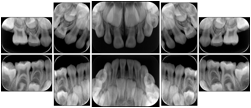

3. A dental provider wishes to capture a series of DICOM IO images for the patient’s dentition. The tooth morphology, teeth are divided into molars, premolars, canines and incisors, and a number of images for each jaw. The anatomic information was captured utilizing the triplet of schema. This standard code sequence is based on ISO 3950-2010, Dentistry - Designation system for teeth and areas of the oral cavity.

Every IO image should have anatomic information either through the primary or modifier sequence.

In most standard cases, images are oriented in structured layouts. These structured displays are useful to be shared between providers for reference purposes.

Table OO.1.1-1 shows structured display standard templates, where Viewset ID is based on the Japanese Society for Oral and Maxillofacial Radiology (JSOMR) classification provided by JIRA (Japan Medical Imaging and Radiological Systems Industries Association, www.jira-net.or.jp). Expected or typical teeth to be imaged location, region and designation codes are based on ISO 3950-2010, Dentistry - Designation system for teeth and areas of the oral cavity. For all the hanging protocols listed in OO.1.1-1, the value to use for Hanging Protocol Creator (0072,0008) is "JSOMR" and the value to use for Hanging Protocol Name (0072,0002) does not include "JSOMR" (e.g., "DL-S001A", not "JSOMR DL-S001A").